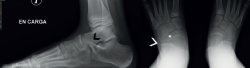

mact.1701.fs2403003-figura5.png

Figura 5. En la proyección axial se intuye la falta de paralelismo entre las superficies articulares. A: en la tomografía axial computarizada se aprecia coalición bilateral, con el drunken waiter sign, en uno de ellos (la bandeja del camarero se inclinaría); C: en la reconstrucción tridimensional se aprecia importante deformidad en el sustentaculum, donde el paciente refería dolor y deformidad.

Drunken waiter sign o signo del “camarero borracho” (Figura 5): si se aprecia en las radiografías axiales del calcáneo de Harris un ángulo superior a 20° entre la superficie del sustentaculum y la posterior, se sospechará una coalición, con una sensibilidad del 72% y una especificidad del 94% que se debe confirmar en cortes coronales de TAC.